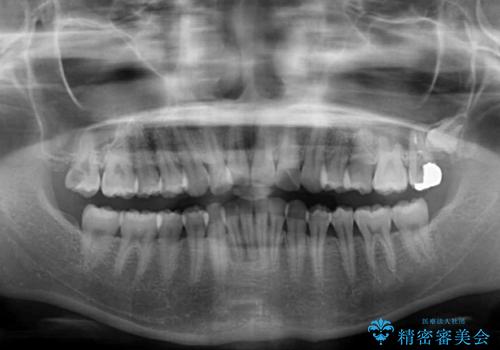

- 前歯2本が飛び出してることを気にして来院された患者様です。

全体的に黄ばんだ歯の色も気になるとのことで、マウスピース矯正により飛び出した前歯を治しつつ、ホームホワイトニングを併用して黄ばみを解消していくこととしました。

歯と歯の間を削ることで、飛び出した前歯が引っ込み、スッキリとした口元となりました。